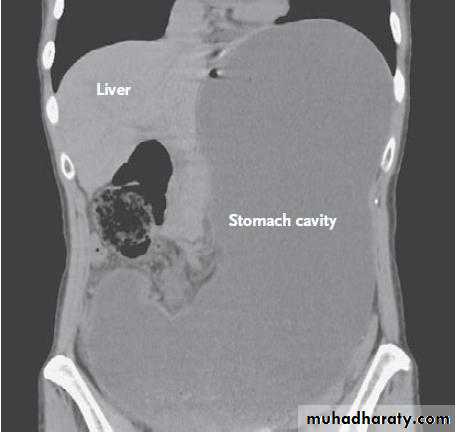

GASTRIC OUTLET OBSTRUCTION

The two common causes of gastric outlet obstruction are gastric cancer and pyloric stenosis secondary to peptic ulceration. gastric outlet obstruction should be considered malignant until proven otherwise.However, in recent years, the most common cause of gastric outlet obstruction has been gastric cancer. In this circumstance the metabolic consequences may be somewhat different from those of benign pyloric stenosis because of the relative hypochlorhydria found in patients with gastric cancer.

A long history of peptic ulcer disease. The pain may become unremitting. The vomitus is totally lacking of bile. Very often it is possible to recognise foodstuff taken several days previously. The patient commonly complains of losing weight, and appears unwell and dehydrated.O/E: It may be possible to see the distended stomach and a succussion splash may be audible.

Investigation of the patient with endoscopy and contrast radiology with biopsy of the area around the pylorus is essential to exclude malignancy.